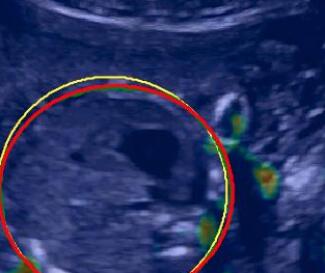

V-C Automated Biometric Measurements

We integrate our shadow confidence maps into an automatic biometric measurement approach [32], and show the biometric measurement performance (measured by DICE) before and after adding shadow confidence maps.

Similar to the ultrasound standard plane classification, shadow confidence maps are integrated into a biometric estimation model described in [32] as an extral channel. Specifically, we train and test four fully convolutional networks with the same hyper-parameters as detailed in [32], and use the same ellipse fitting algorithm described therein. The first network is trained only on the image data used in [32]. The other three networks are trained with an additional input channel for shadow confidence maps that are separately generated by the baseline, the proposed, and the proposedAG method.

We show three examples that are affected by shadows, and show their biometric measurement results in Table V. From this experiment, we find that biometric measurement performance is boosted by up to for problematic failure cases after adding shadow confidence maps. The average performance on the entire test data set stays almost the same since only a small proportion of the test images are affected by strong shadows, mainly because of the image acquisition by highly skilled sonographers.